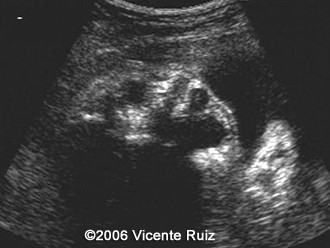

This is a case of dacryocystocele in a third  trimester fetus. Note the cystic mass between the right medial cantus and the nose.